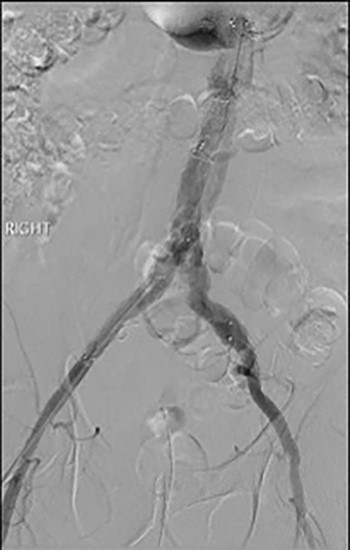

Post-lysis CT scanning showing fully re-canalized aorto-iliac system.

The patient was transferred to the high-dependency unit for observation during the thrombolysis. After 4-h, the patient was taken back to Interventional Radiology department for a check angiogram (Fig. 3). This demonstrated a fully re-canalized aorto-iliac system with no distal thrombotic or embolic complications. The thrombolysis infusion was stopped at this stage. In the post-operative period, anticoagulation has been continued with Apixaban. A CT scan 6 weeks post-procedure has confirmed ongoing patency of the endograft with no visible thrombus (Fig. 4).